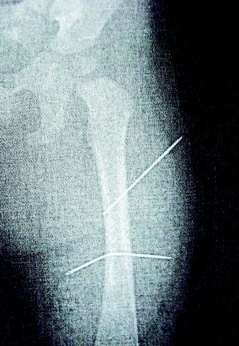

判決書指出,該女子去年照顧年僅9個(gè)月大外甥女,因外甥女哭鬧不停,情緒失控下拿家中縫衣針兩根,連刺入女娃左大腿內(nèi)側(cè),完全沒(méi)入皮下組織。

隔月27日,該女子又見外甥女哭鬧不停,拿蒼蠅拍朝著外甥女背部連打數(shù)十下,造成女娃背部瘀傷。經(jīng)女娃母親發(fā)現(xiàn)后送醫(yī)救護(hù),院方為女童進(jìn)行X光片照射后,才發(fā)現(xiàn)女娃左大腿里竟有兩根縫衣針。